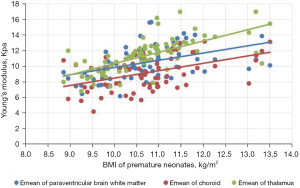

Comparison of Emean of the neonatal brain between premature neonates and full-term neonatesVariables Premature neonates (n=76) Full-term neonates (n=83) Left (kPa) Right (kPa) Mean (kPa) Left (kPa) Right (kPa) Mean (kPa) Lateral paraventricular white matter 10.39±2.10a 10.23±2.08a 10.50±2.04a 12.32±2.14 12.65±2.09 12.49±1.91 Thalamus 11.14±2.33a 11.25±2.07a 11.38±2.16a 13.31±2.49 12.92±2.40 13.11±2.22 Choroid 9.18±2.19a 9.15±2.17a 9.16±2.07a 9.65±2.24 9.62±2.20 9.64±2.08 a, P<0.001 premature neonate group vs. full-term neonate group. Emean, elasticity modulus. - The Pearson’s correlation coefficient analysis showed that the neonatal lateral paraventricular brain white matter, thalamus, and choroid brain tissue stiffness values were significantly and positively correlated with BMI (P<0.05). The correlation coefficients between the lateral paraventricular brain white matter, thalamus, and choroid and BMI were r=0.457, r=0.681, and r=0.462, respectively, for the premature neonate group and r=0.476, r=0.327, and r=368, respectively, for the full-term neonate control group (see Figures 2,3

).

The gray matter of the brain is the dense site of neuronal cell bodies, and the white matter of the brain is the site of nerve fiber aggregation. When the thalamic elastic stiffness values are higher than the white matter stiffness values in the neonatal period, the gray matter structure is denser than the white matter structure of the brain. The development of the central nervous system is an extremely complex and continuous process that involves a dynamic balance between cell proliferation, differentiation, migration, synaptogenesis, myelin formation, and apoptosis of brain neurons and glia. Examinations of correlations between brain tissue stiffness and the degree of cerebral vascular development and cerebral blood perfusion pressure have shown that the denser the neuronal cells, the higher the value of brain tissue stiffness (17). In this study, we analyzed correlations between BMI and brain tissue Emeans in premature and full-term neonates, and found that the higher the BMI, the higher the neonatal thalamus, lateral paraventricular cerebral white matter, and choroid plexus tissue stiffness. Pong et al. (18) used Magnetic resonance elastography (MRE) to examine the cranial brains of rats at 1–6 weeks, and the results suggested that the brain gray matter stiffness of young rats increases with age. Which provides support for the results of the present study.